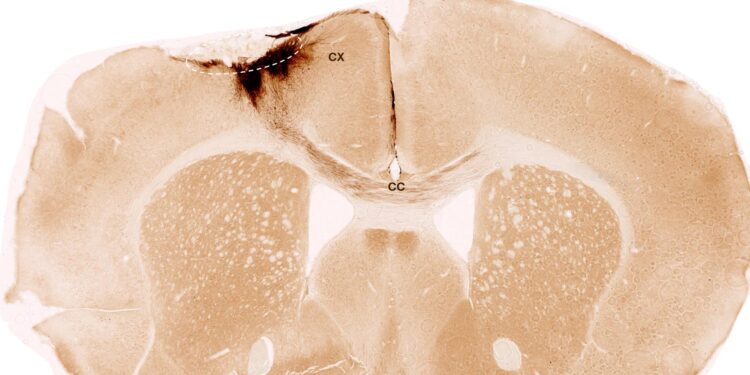

The research employed human neural stem cells, from which completely different cell varieties of the nervous system can type. The stem cells had been derived from induced pluripotent stem cells, which in flip could be manufactured from regular human somatic cells. For his or her investigation, the researchers induced a everlasting stroke in mice, the traits of which intently resemble the manifestation of stroke in people. The animals had been genetically modified in order that they might not reject the human stem cells.

One week after stroke induction, the analysis workforce transplanted neural stem cells into the injured mind area and noticed subsequent developments utilizing quite a lot of imaging and biochemical strategies. “We discovered that the stem cells survived for the total evaluation interval of 5 weeks and that almost all of them remodeled into neurons, which really even communicated with the already present mind cells,” Tackenberg says.

The researchers additionally discovered different markers of regeneration: new formation of blood vessels, an attenuation of inflammatory response processes, and improved blood-brain barrier integrity. “Our evaluation goes far past the scope of different research, which centered on the speedy results proper after transplantation,” Tackenberg explains. Fortuitously, stem cell transplantation in mice additionally reversed motor impairments brought on by stroke. Proof of that was delivered partly by an AI-assisted mouse gait evaluation.